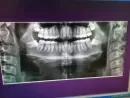

Возможно ли не удалять ретинированные 8-ки без вреда для 7-ок?

На рентген снимке обнаружены горизонтально расположенные, ретинированные восьмерки. Стоматолог-терапевт говорит их удалять. Много начиталась ужасного, знаю о последствиях, если их оставить, но все равно страшно боюсь последствий операции. Оставить боюсь, удалять еще страшнее. Врач сказала, что верхние 8-ки можно оставить, что еще они могут вырасти ровно, что это не нижняя челюсть.

И стоит ли удалять верхние? Возможно ли в моем случае есть шанс их оставить без вреда семеркам?

Оставить их можно, но полноценно зубы никогда не прорежутся. На пути прорезывания они будут доставлять сильный дискомфорт, вплоть до контрактуры. Помимо этого могут привести к скученности во фронтальном отделе зубов нижней челюсти, также могут пострадать седьмые зубы. Как правило, при таком расположении зубы рекомендуют удалить.